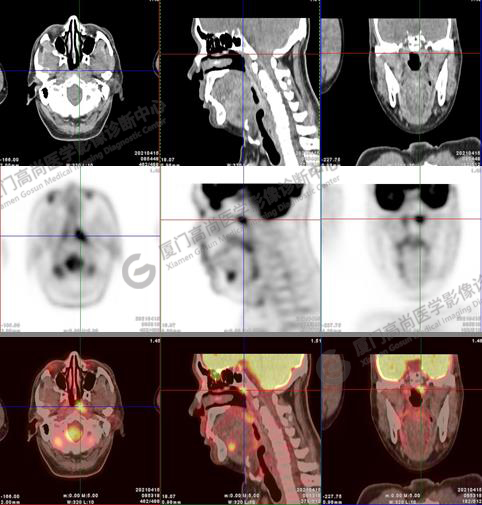

PET/CT影像圖

圖1:PET/CT全身圖像

圖2:雙側(cè)頸部多發(fā)增大淋巴結(jié),代謝不同程度增高,考慮為轉(zhuǎn)移。

圖6-9:鼻咽左側(cè)壁增厚,代謝異常增高,考慮為鼻咽癌